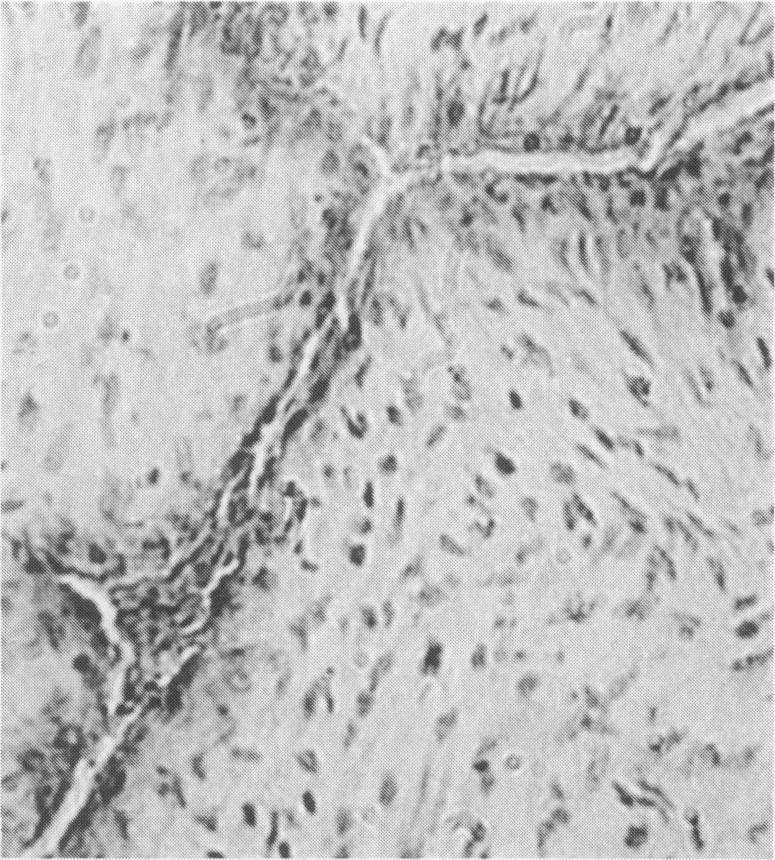

Immunocytochemistry has been used to identify endothelial cells in sections of human umbilical cord and in cultures of the venous and arterial endothelium, using Factor VIII and Ulex europaeus as endothelial markers. The connective tissue components, including various collagen types, fibronectin and laminin, were identified and localized in the cord and in both venous and arterial cultured endothelium. Interstitial collagens synthesized by the cultured cells were isolated and quantified. Angiogenic ability was examined. The effect of a noxious stimulus, 24 h hypoxia, was quantified in cultured venous endothelium. The results showed that cultured arterial endothelium possesses a vacuolated cytoplasm which is absent in venous endothelium. The major collagens observed in venous culture were types III and V; the latter was found mainly in the cell layer. Venous endothelium was angiogenic. It responded to hypoxia by producing fewer cells, more protein/10(6) cells but less collagen, both in absolute terms and as a percentage of protein/10(6) cells, thus behaving like cultured porcine and bovine aortic endothelium. Fibronectin was the major 'glue' associated with endothelium. We conclude that culture can reveal the synthetic potential of endothelium which the cord itself does not often show; moreover culture appears essential to demonstrate that arterial and venous endothelium behave differently from each other.